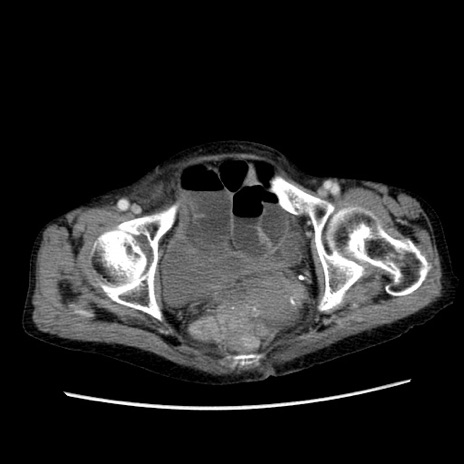

症例25(横断像)

【症例】80歳代女性

【主訴】胸のつかえ感

【現病歴】約9時間前に食後から胸のつかえた感じあり、嘔吐あり、来院。

【既往歴】胃癌(全摘)、胆摘、虫垂炎

【身体所見】心窩部に圧痛あり、反跳痛なし。

【データ】WBC 5700、CRP 0.05